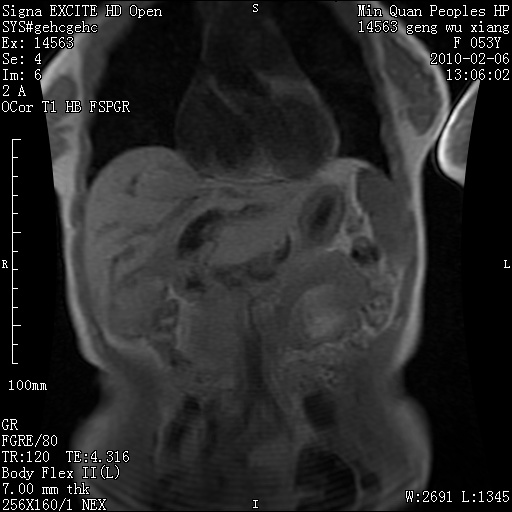

标题: MRI2762:胆道梗阻原因?

f,53y,全身黄染多日。

高位胆道梗阻 胆管癌可能性大

支持 高位胆道梗阻 胆管癌可能性大。